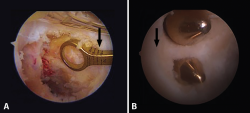

• Posterior drawer test. This is done with the patient in supine decubitus and the knee in 90° flexion. The test involves the application of pressure in a posterior direction of the proximal region of the tibia, observing posterior tibial translation in the injured knee with respect to the contralateral knee (Figure 2). A posterior displacement of the tibia of 0-5 mm is considered to correspond to a grade I lesion, 6-10 mm to a grade II lesion and >10 mm to a grade III lesion. Assessment of the degree of displacement is subjective, and thus implies important interobserver variability. If the tibial plateau remains located anterior to the medial femoral condyle, the lesion is considered to correspond to grade I, while if it is located at the same level as the femoral condyle the lesion corresponds to grade II, and if the plateau extends beyond the medial femoral condyle, the lesion corresponds to grade III (Figure 2)(10,11).

Figure 2. Initial position of the tibia reduced in the posterior drawer manoeuvre (A) compared with posterior tibial translation without reduction (B).

Posterior translation of the tibia is measured as the minimum distance between a line tangential to the posterior cortical layer of the tibia and another line tangential to the posterior margin of the femoral condyle at the most dorsal point of the Blumensaat line (Figure 5)(12,13).